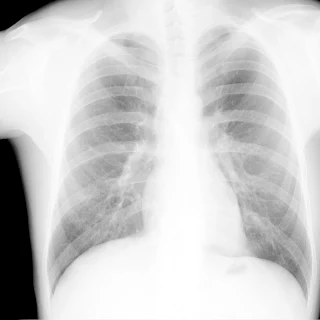

Легені без вогнищево - інфільтративних змін. Корені не змінені. Синуси вільні. Серце норма.